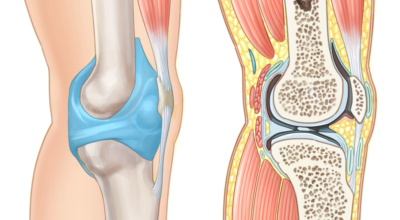

콘드로이틴을 말하는것으로 골 관절염의 관절 질환 치료에 글루코사민과 동반해 사용되는 물질의 성분입니다. 콘드로이친은 탄수화물의 한 종류로 연골 탄성섬유의 중요한 주물질입니다. 상어의 연골에 들어 있는 물질으로 신체의 관절, 연골, 피부에 적은 양으로 존재하는 물질이라고 알려져 있습니다. 콘드로이친은 연골의 파괴를 예방하고 새 연골 생성을 활성화하는데 많은 도움되는 것으로 알려져 있습니다.

글루코사민에 대조해 원료가 100배가량 비싼 고가의 원료인것으로 알려져 있답니다. 관절염 이유가 되는 것으로는 관절 연골이 닳아 없어지기 때문인데 퇴행성 질환이라고 하는 이유가 연골이 더 이상 생성되기 어렵기 때문이죠. 특히 콘드로이친이라 하는 성분이 나이가 들면서 길이가 짧아지고, 크기가 줄어들기 때문에 연골 구조가 변화되어 가면서 무릎뼈의 간격이 좁아져 통증을 유발하는 원인이 되는데 이 경우에 콘드로이친 효능을 바라볼 수 있답니다.

콘드로이친 효능 중 가장 대표적인 것이 연골세포를 보존하는 역할이라고 합니다. 콘드로이친에는 연골세포의 분해를 억제시켜 연골세포를 보호해주며 유지시켜주는 기능이 있습니다. 연골은 노화가 진행될수록, 나이가 들 수록 점점 그 크기가 떨어지거나 끊어질 수 있지만 이 때에 콘드로이친이 그 스펀지와 같은 역할을 하여 연골 속 수분을 잡아주어 부드럽고 유연하게 유지할 수 있게 도와준다고 알려져 있답니다.

하지만 콘드로이친은 육체 내에서 자연적으로 생성을 할 수 없어 외부에서 추가적으로 보충되어줘야 하는데 나이가 들면서 점점 콘드로이친이 부족하게 되면 무릎이나 손목의 통증, 관절염 등 자연 노화로 인해 피할 수 없이 오는 질환들이 생길 수 있다고 하네요. 그뿐 아니라 아침에 일어났을 때 주로 일어나는 관절 경직 증상 완화에도 큰 도움을 줍니다.